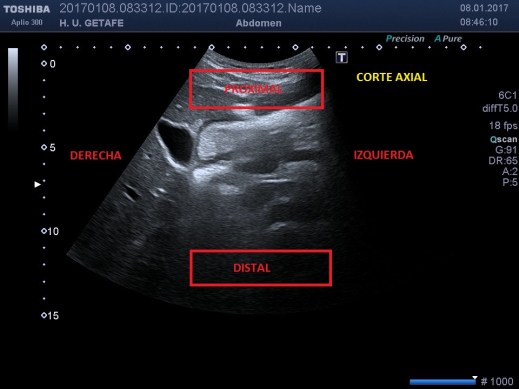

Muy bien, pero ¿cómo se consigue la imagen de ecografía? Es decir, ¿cuales son los planos de corte?

La base está en la colocación del transductor. La sonda que estemos usando tiene colocarse de manera que la derecha del paciente se sitúe a la derecha de la imagen en nuestro monitor, que corresponde a nuestra mano izquierda, si estamos realizando un corte axíal, para ello, tocaremos en uno de los dos lados de la huella (la parte gris) de la sonda con un dedo con un poco de gel y con la imagen descongelada, una vez que veamos en la pantalla donde se mueve nuestro dedo comprobaremos si ese movimiento marca la derecha de la imagen, entonces si es así, pondremos ese lado de la sonda a la derecha del paciente, si no,giraremos la sonda. De este modo, la derecha del paciente será la derecha de nuestro monitor.

Corte axial.

En esta imagen, vemos colocado todo correctamente, la vesícula a la derecha de la imagen y el hígado también, si hubiésemos colocado mal la sonda en este corte axial, el hígado aparecería a la izquierda de la imagen.

Si el corte es longitudinal, igual, pero en este caso haremos coincidir la sonda con la parte que corresponda a la derecha de la imagen y la zona craneal del paciente, así tendremos que la derecha de la pantalla es la parte craneal del paciente y la izquierda, la zona caudal.